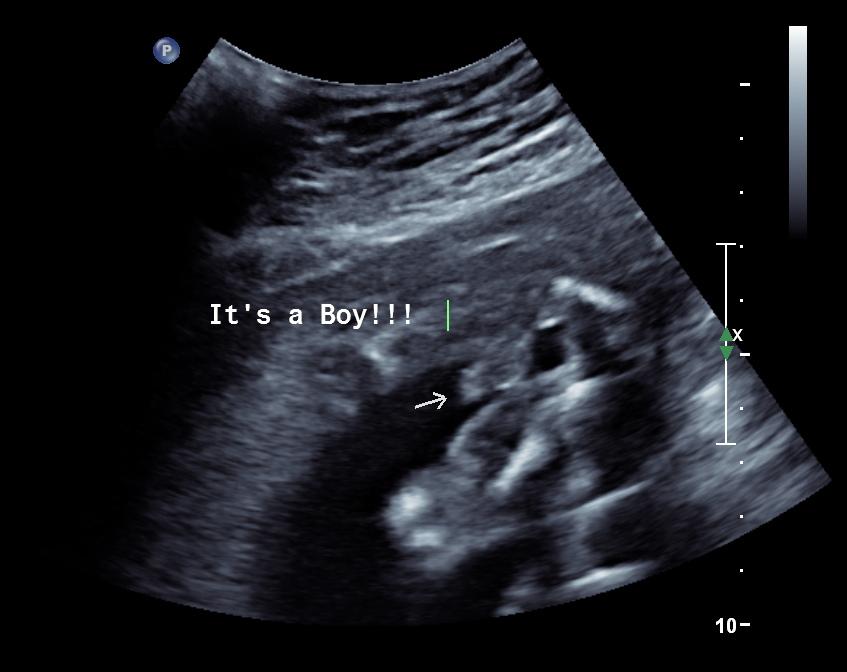

It's a Boy!!!

We are really excited that we are having another boy. We have all the clothes and they can share a room. I hope they have fun playing together...eventually. The ultrasound went great. Austin didn't really care what was going on. At first he was worried we were there for him but then he realized it was my appointment. He patted my arm and said "It's ok Mommy." Then when we saw the baby he just stared at the screen. The baby kept his little hand up near his face. I wonder if he will be a binki baby. When we left he said "Thank you Much." I can't wait to see my new baby boy. We are leaning towards the name Bennett William Kennington.